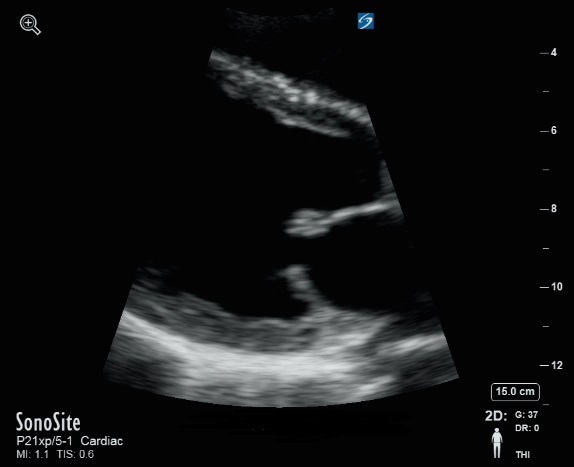

二尖瓣缩放